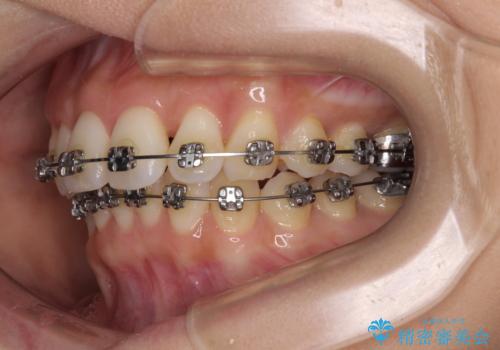

- 矯正装置

- メタルブラケット

奥歯の噛み合わせをみると、上顎歯列が全体的に前突している状態であり、この咬み合わせのまま歯列を整えると出っ歯になってしまう可能性がありました。

アンカースクリューと補助装置を使用して上顎大臼歯を遠心移動させることで咬み合わせを改善し、ワイヤー装置によりデコボコを解消しながら口元の突出感も改善していくこととしました。

出っ歯になることなく、上下前歯が綺麗に接触する状態で仕上げることができました。